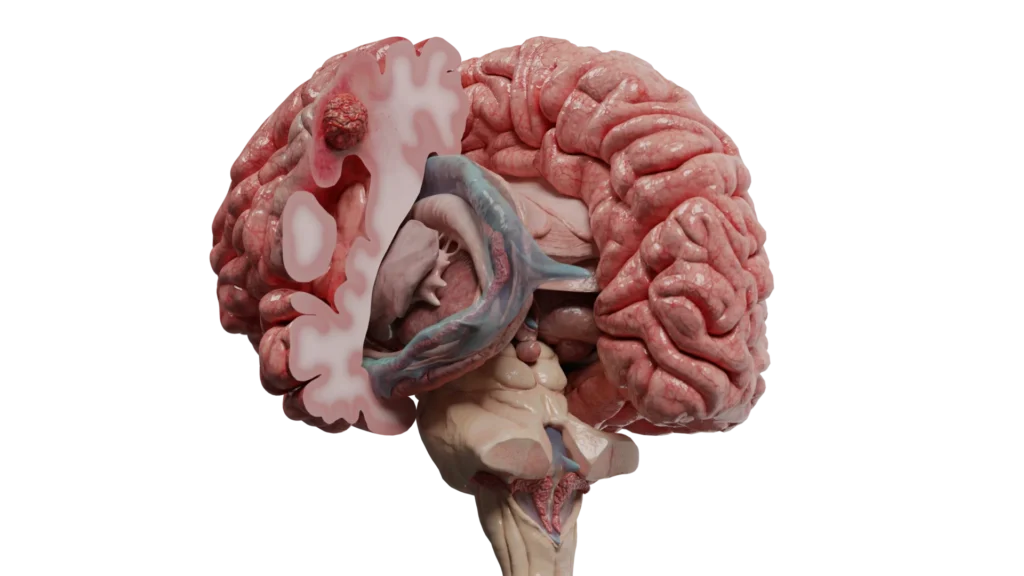

A metástase cerebral é um tumor cerebral secundário que se origina quando células cancerígenas de um tumor primário localizado em outra parte do corpo se disseminam e alcançam o cérebro, onde formam novos tumores.

Como Ocorre a Metástase Cerebral?

1. Via Hematogênica (Mais Comum)

Através da corrente sanguínea:

• Células cancerígenas se desprendem do tumor primário

• Entram na corrente sanguínea

• Viajam pelo sistema circulatório

• Alcançam o cérebro através das artérias

• Extravasam dos vasos sanguíneos

• Invadem o tecido cerebral

• Proliferam e formam novos tumores